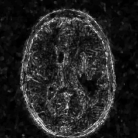

The reconstructions of a 256×256256256256\times 256 brain image from its radial samples acquired with a 40 spoke trajectory are shown in Fig. 6. The measurements are corrupted with zero mean complex Gaussian noise of standard deviation σ=18.8𝜎18.8\sigma=18.8. All methods result in loss of subtle image features since the acceleration factor and the noise level are high. We observe that the NLS scheme provides better recovery than the competing methods. The quantitative results in this setting for various MR images are shown in the bottom section of Table IV. We observe that the SNR improvement offered by NLS over the other methods are not as high as in the previous cases, mainly due to the considerable noise in the data and the high acceleration.

Refer to caption

(a) Original

(b) DLMRI,SNR=17.46

(c) TV,SNR=17.43

(d) NLS,SNR=18.46

(e) Sampling pattern

(f) DLMRI error

(g) TV error

(h) NLS error

Figure 6: Comparison of the algorithms in the presence of noise. We consider the recovery of a 256×256256256256\times 256 original MRI brain image from its radial trajectory with 40 spokes, contaminated by Gaussian noise with standard deviation σ=18.8𝜎18.8\sigma=18.8. The error images are magnified by a scale of 5 fold for the best visibility. This is a challenging case due to the high undersampling factor and high measurement noise. We observe that the NLS scheme provides the best overall reconstructions.